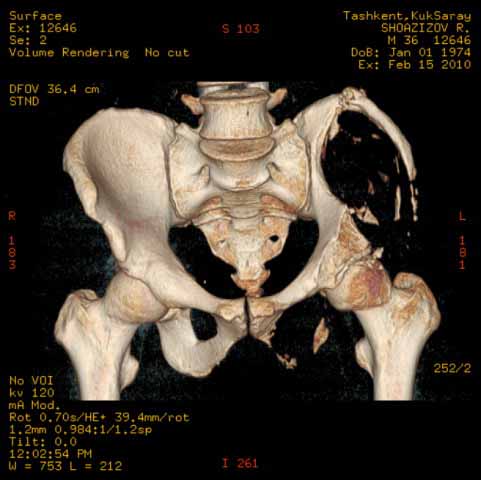

Могу пока выложить еще снимки и показать хронологию данного процесса и его прогрессирование, первый снимок был 2011 года. Вот этот 2009

И 2010 год

Также структуру поражения кости можно увидеть на обычных рентгенограммах таза или Компьютерно-Томографических срезах. Трехмерные снимки, кроме красивой картины, не добавляют информации, и самым главным информативным является МРТ, которая покажет структуру ячеек.